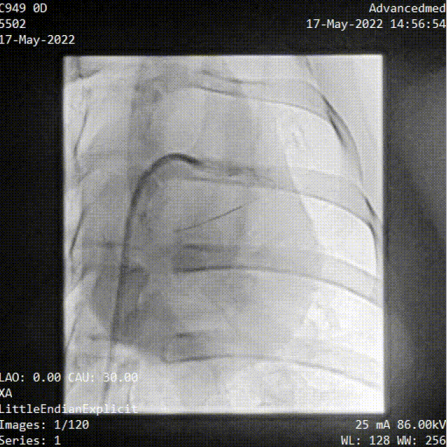

(冠脈導(dǎo)絲遞進(jìn))